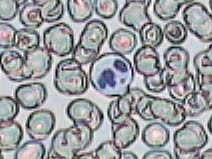

Práctica de Frotis sanguíneo 33